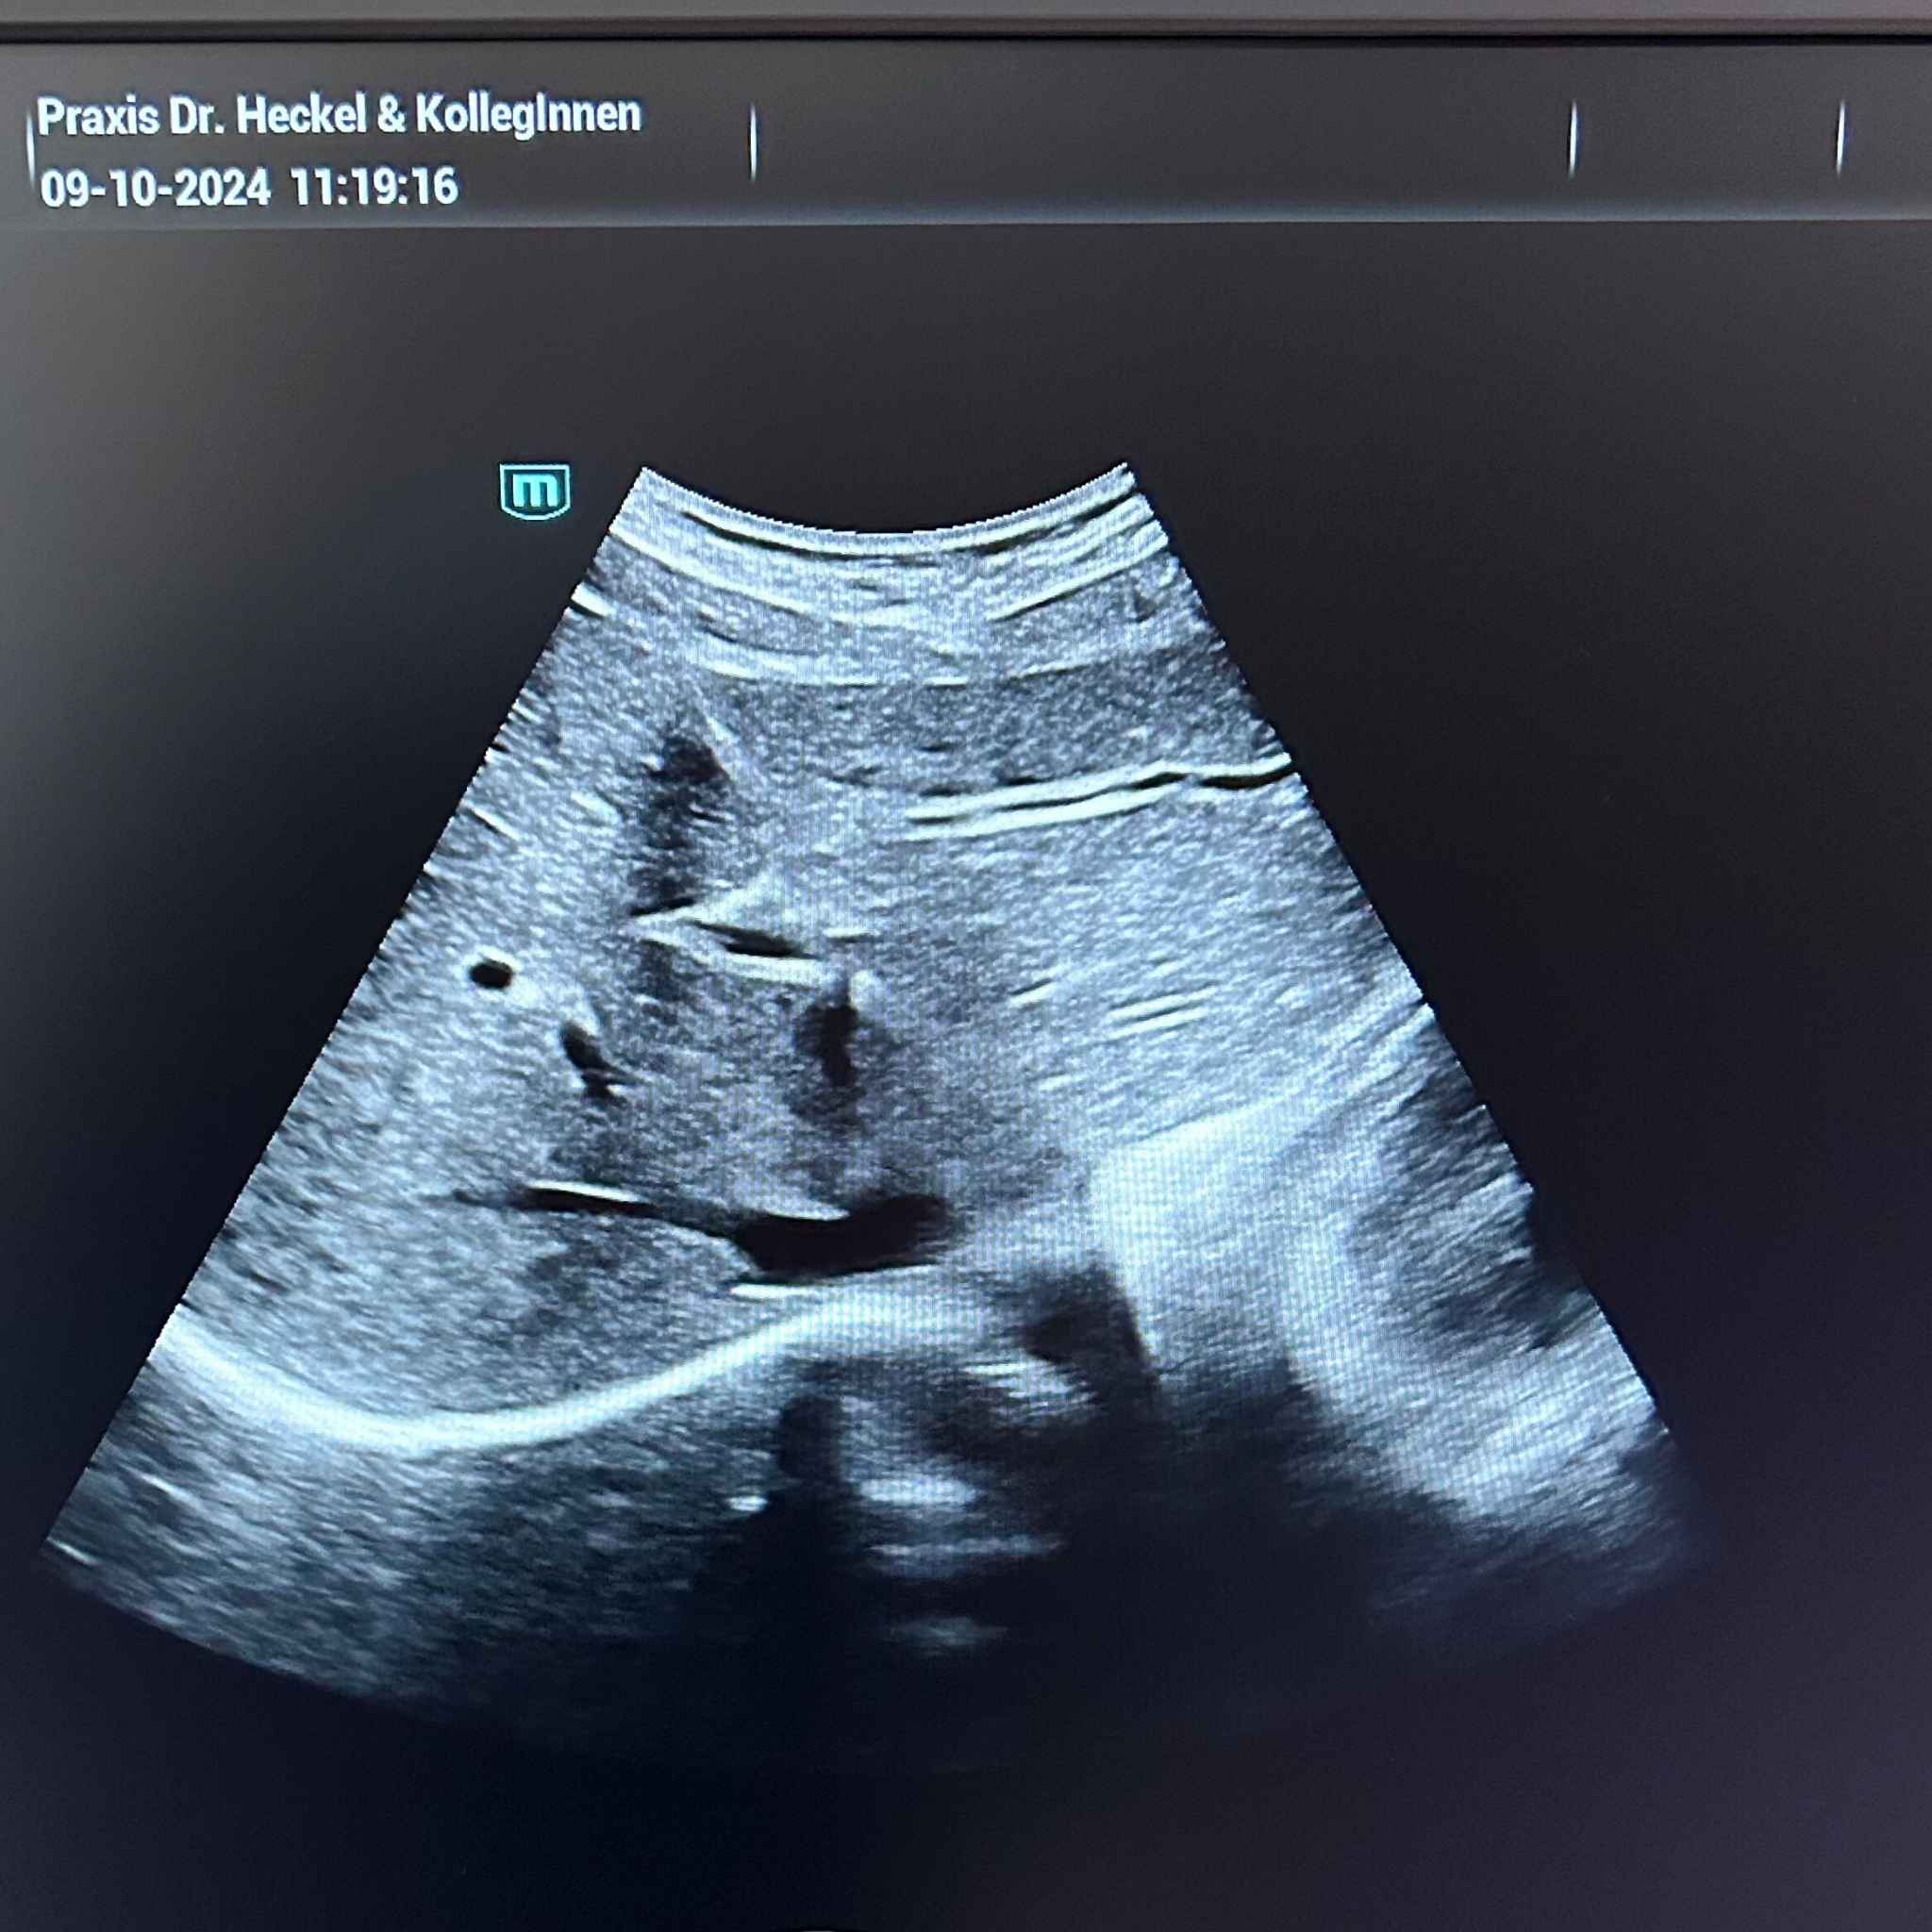

Die Abdomensonografie ist eine bildgebende Untersuchung zur Darstellung der inneren Organe im Bauchraum. Dabei werden Ultraschallwellen verwendet, um Bilder der Leber, der Nieren, der Milz, der Gallenblase, der Bauchspeicheldrüse sowie den Blutgefäßen und Lymphknoten zu erstellen. Diese Methode ist schmerzfrei, nicht-invasiv und wird häufig zur Diagnose und Überwachung von Erkrankungen des Bauchraums eingesetzt. Aufgrund ihrer Vielseitigkeit und Sicherheit ist die Abdomensonografie eine der am häufigsten verwendeten Methoden in der Innere Medizin und Allgemeinmedizin.

- Durchführung: Der Arzt bewegt den Ultraschallkopf über den Bauch des Patienten, um verschiedene Organe und Strukturen zu untersuchen. Es gibt einen standardisierten Untersuchungsablauf. Die Ultraschallwellen durchdringen die Bauchdecke und werden von den inneren Organen zurückgeworfen. Diese zurückgeworfenen Wellen werden von einem Computer in Echtzeit in Bilder umgewandelt, die auf einem Monitor dargestellt werden. Die Untersuchung dauert in der Regel 15 Minuten.

Die Auswertung der Abdomensonografie erfolgt durch eine detaillierte Analyse der aufgezeichneten Bilder. Der Arzt achtet dabei auf die Größe, Form und Struktur der Organe, um eventuelle Erkrankungen oder Abnormalitäten zu diagnostizieren. Besonderes Augenmerk wird auf die Gewebestruktur, das Vorhandensein von Steinen, Zysten, oder Tumoren, sowie auf die Durchblutung der Organe gelegt.